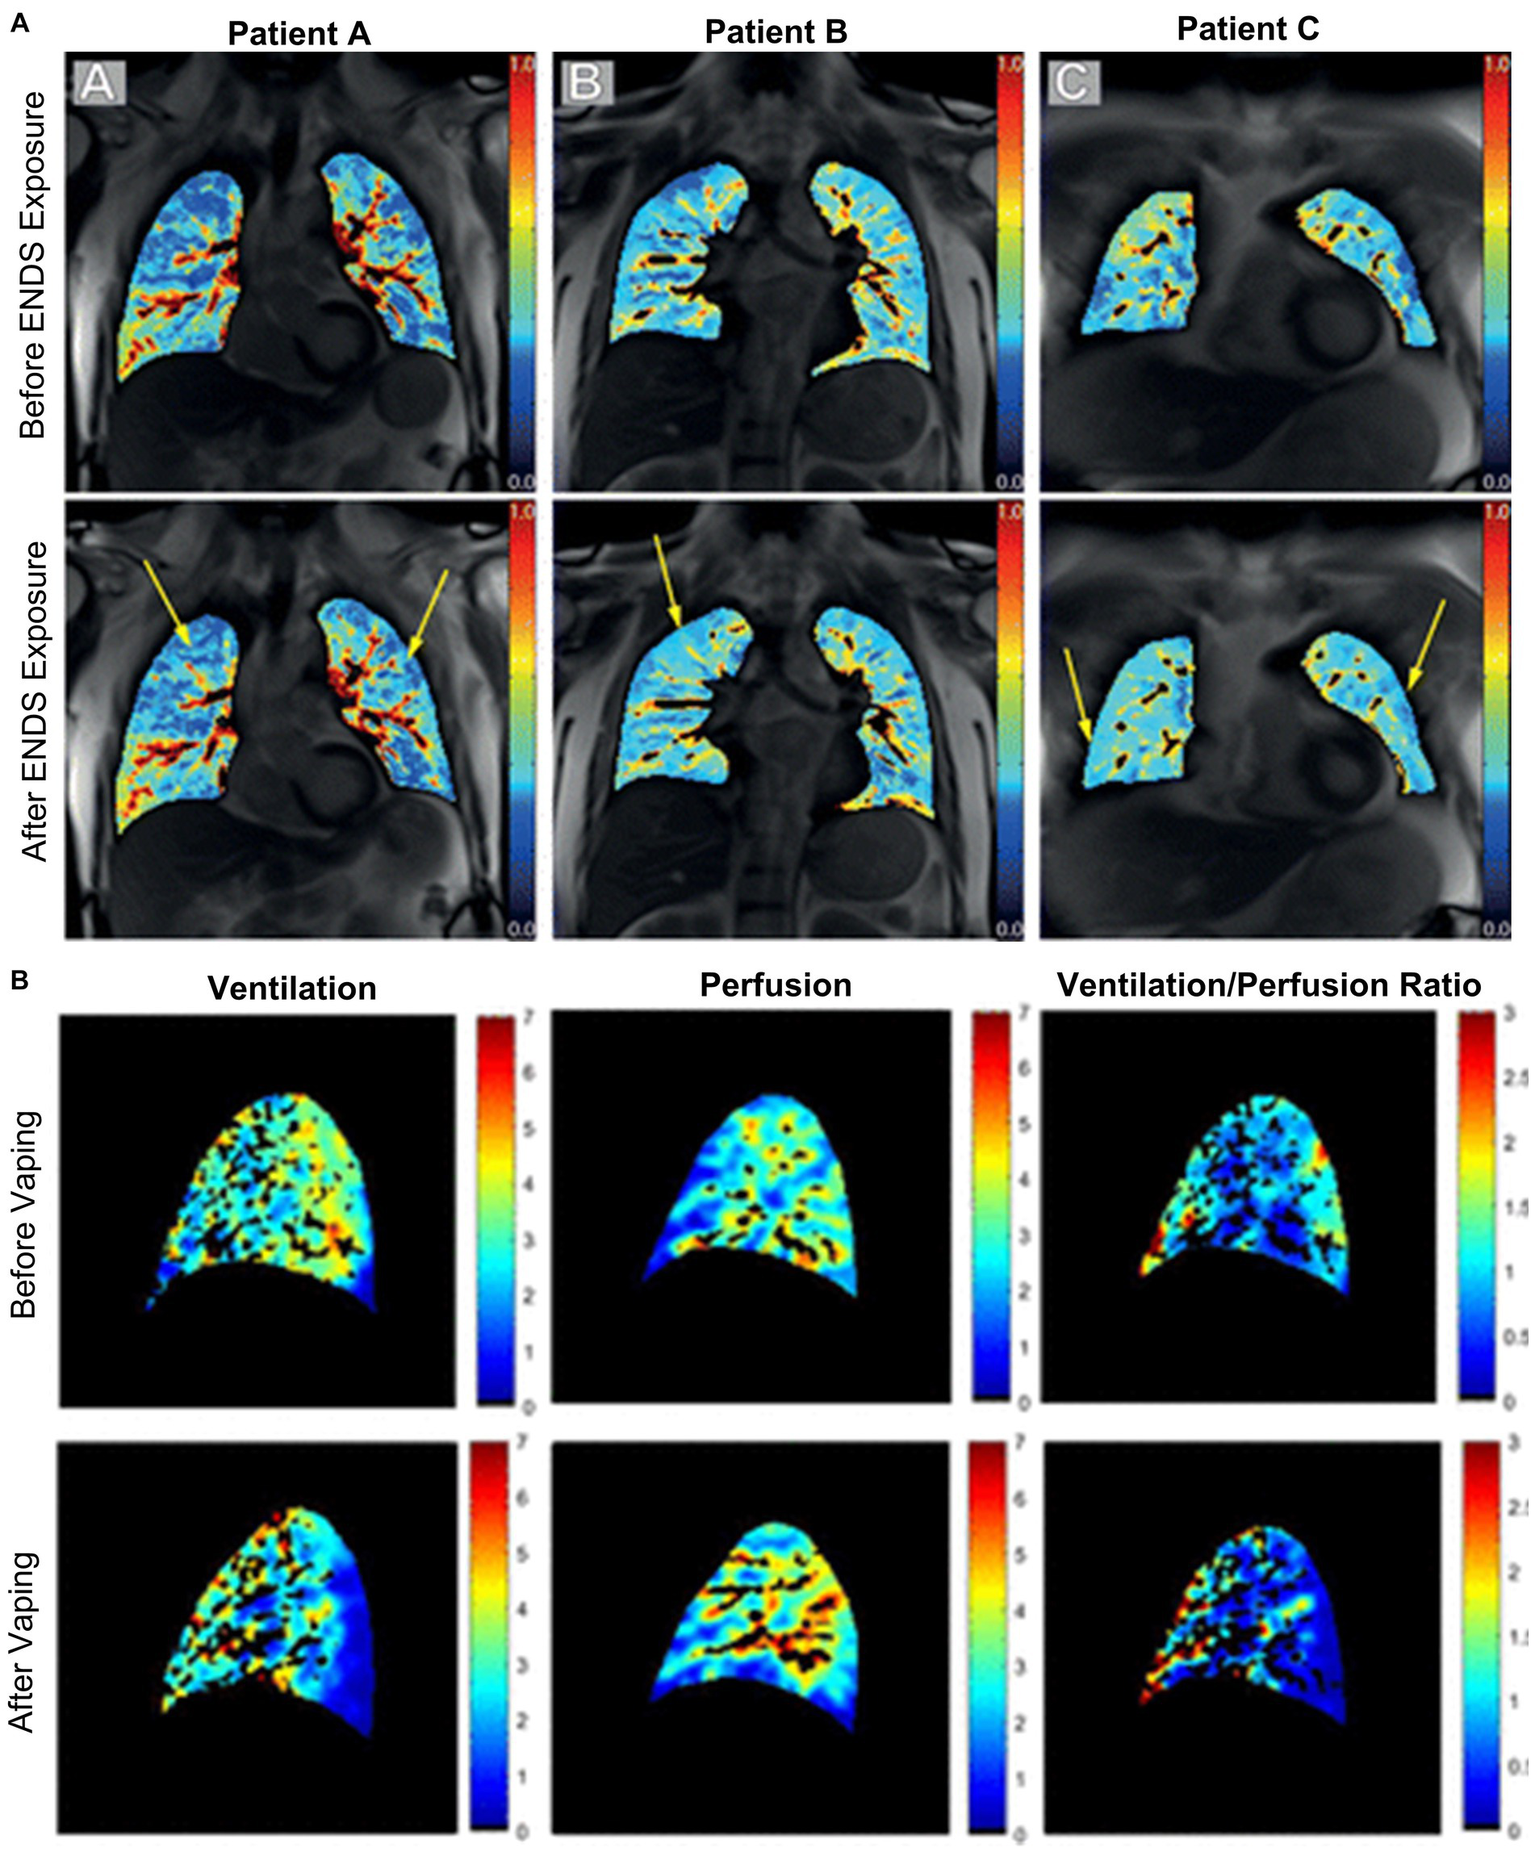

MRI perfusion maps are shown for four e-cigarette users in Figure 9, demonstrating changes in regional perfusion following exposure to e-cigarettes. Two studies have evaluated pulmonary perfusion in e-cigarette users prior to and following acute exposure to e-cigarettes and both observed similar findings. Perfusion prior to exposure was similar between healthy controls and e-cigarette users, and following exposure, perfusion was increased (107) while perfusion heterogeneity was decreased (108). Furthermore, e-cigarette users who were exposed to nicotine-based e-liquids demonstrated significant increases in perfusion while those who were exposed to nicotine-free e-liquids were not. Finally, ventilation/perfusion heterogeneity was increased throughout the lungs of e-cigarette users as compared to healthy controls, both prior to and following acute exposure to e-cigarettes (107); the extent of this disruption in ventilation/perfusion matching was similar to what has previously been observed in COPD.

Figure 9

Free-breathing 1H MRI of acute effects of vaping. (A) Pulmonary perfusion images obtained by using non-contrast matrix pencil MRI in three electronic nicotine vape users before and after exposure. The arrows indicate lung regions with increased regional perfusion post-exposure. Red corresponds to greater perfusion amplitude and blue corresponds to lower values (108). (B) Spatial maps of ventilation, perfusion, and ventilation-perfusion ratios, before and after vaping, in a single sagittal slice of one representative subject. Black regions within the lung field represent regions excluded from analysis, including conducting airways and vessels, and regions with poor signal to noise (107).